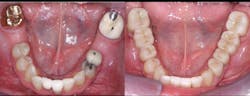

• Use resin-modified glass ionomer (RMGI) cement for zirconia restorations when the tooth preparations have near-optimum characteristics. See Figures 4 through 6 for examples of these characteristics. Most clinicians and researchers would agree that the tooth preparation should be at least 4 mm in height from the gingival margin to the occlusal table, and that the lack of parallelism of the preparation walls should be up to, but not more than, 20 degrees from the long axis of the tooth being prepared.

Figures 4-6: Images showing an adequate impression, the die of an adequate tooth preparation, and the resultant full-zirconia crowns.

Figure 6